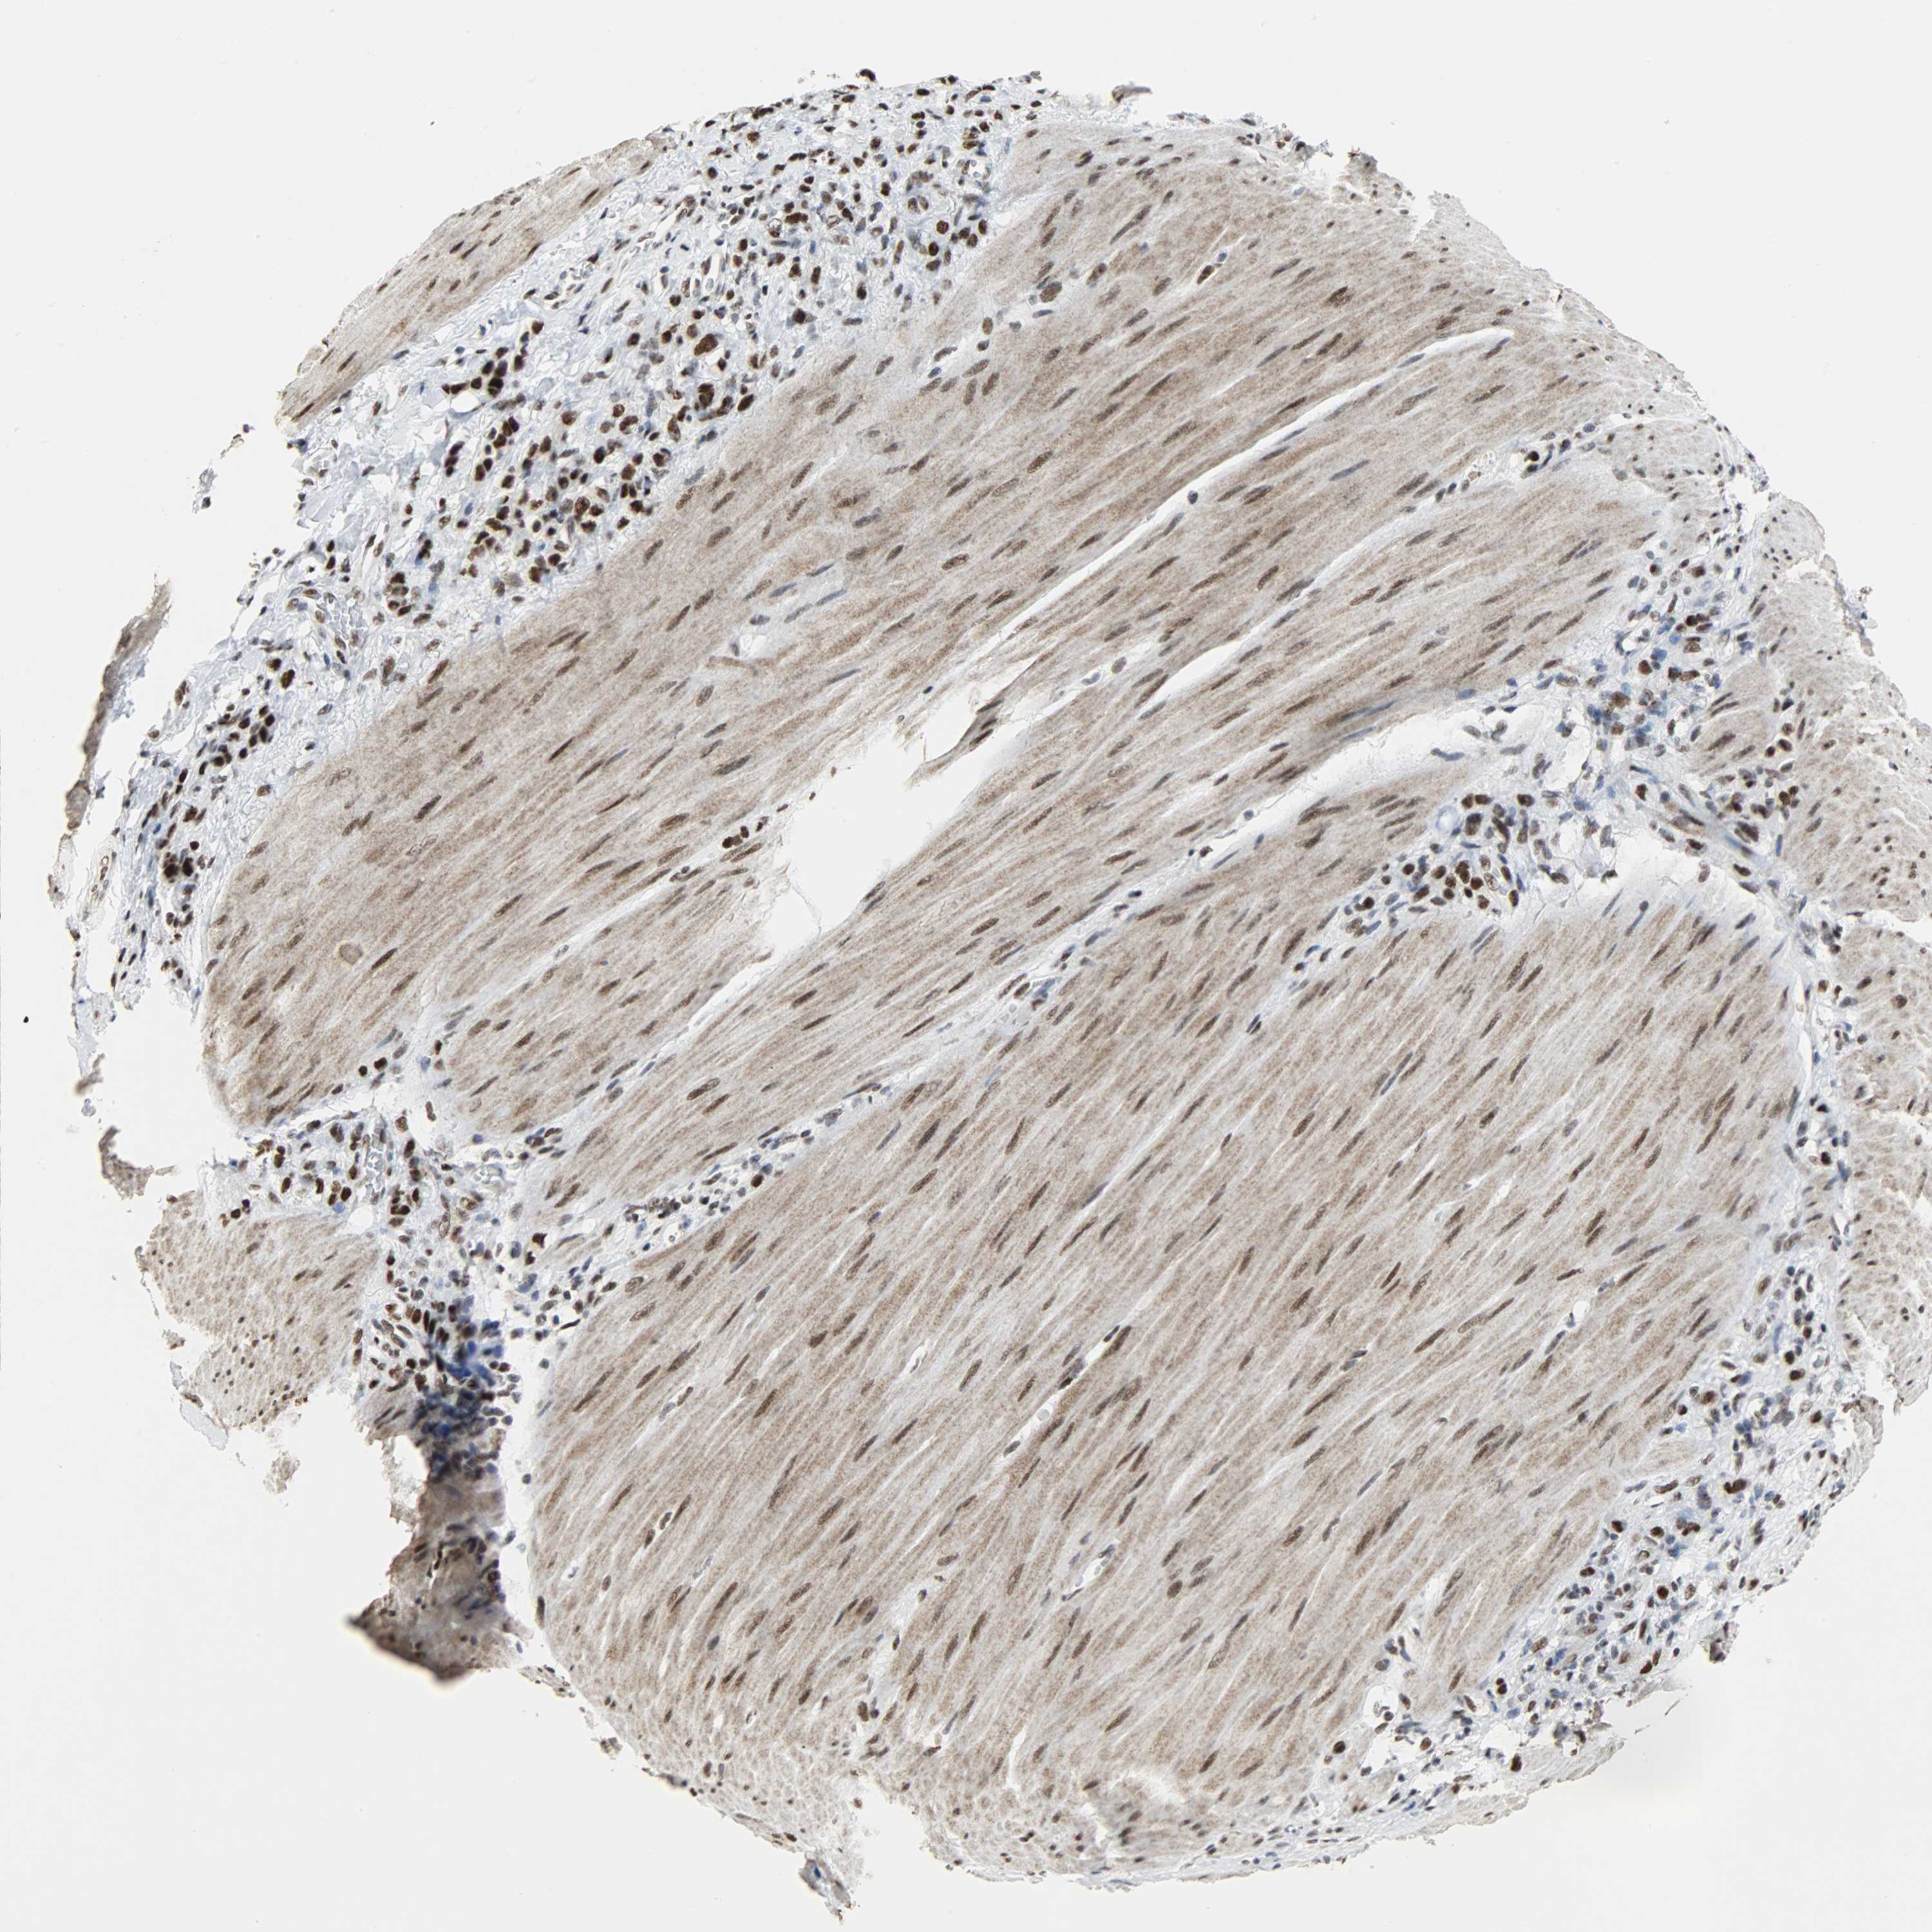

STOMACH CANCER - Protein expressioni

A mouse-over function shows sample information and annotation data. Click on an image to view it in a full screen mode. Samples can be filtered based on level of antibody staining by selecting one or several of the following categories: high, medium, low and not detected. The assay and annotation is described here.

Antibody stainingi

Antibody staining in the annotated cell types in the current human tissue is reported as not detected, low, medium, or high, based on conventional immunohistochemistry profiling in selected tissues. This score is based on the combination of the staining intensity and fraction of stained cells.

Each image is clickable and will lead to virtual microscopy that enables deeper exploration of all samples and also displays staining intensity scores, fraction scores and subcellular localization as well as patient and tissue information for each sample.

Antibody HPA017287

Antibody CAB004643

Staining

High

Medium

Low

Not detected

Intensity

Strong

Moderate

Weak

Negative

Quantity

>75%

75%-25%

<25%

None

Location

Nuclear

Cytoplasmic/membranous

Cytoplasmic/membranous,nuclear

Adenocarcinoma, NOS

Adenocarcinoma, High grade